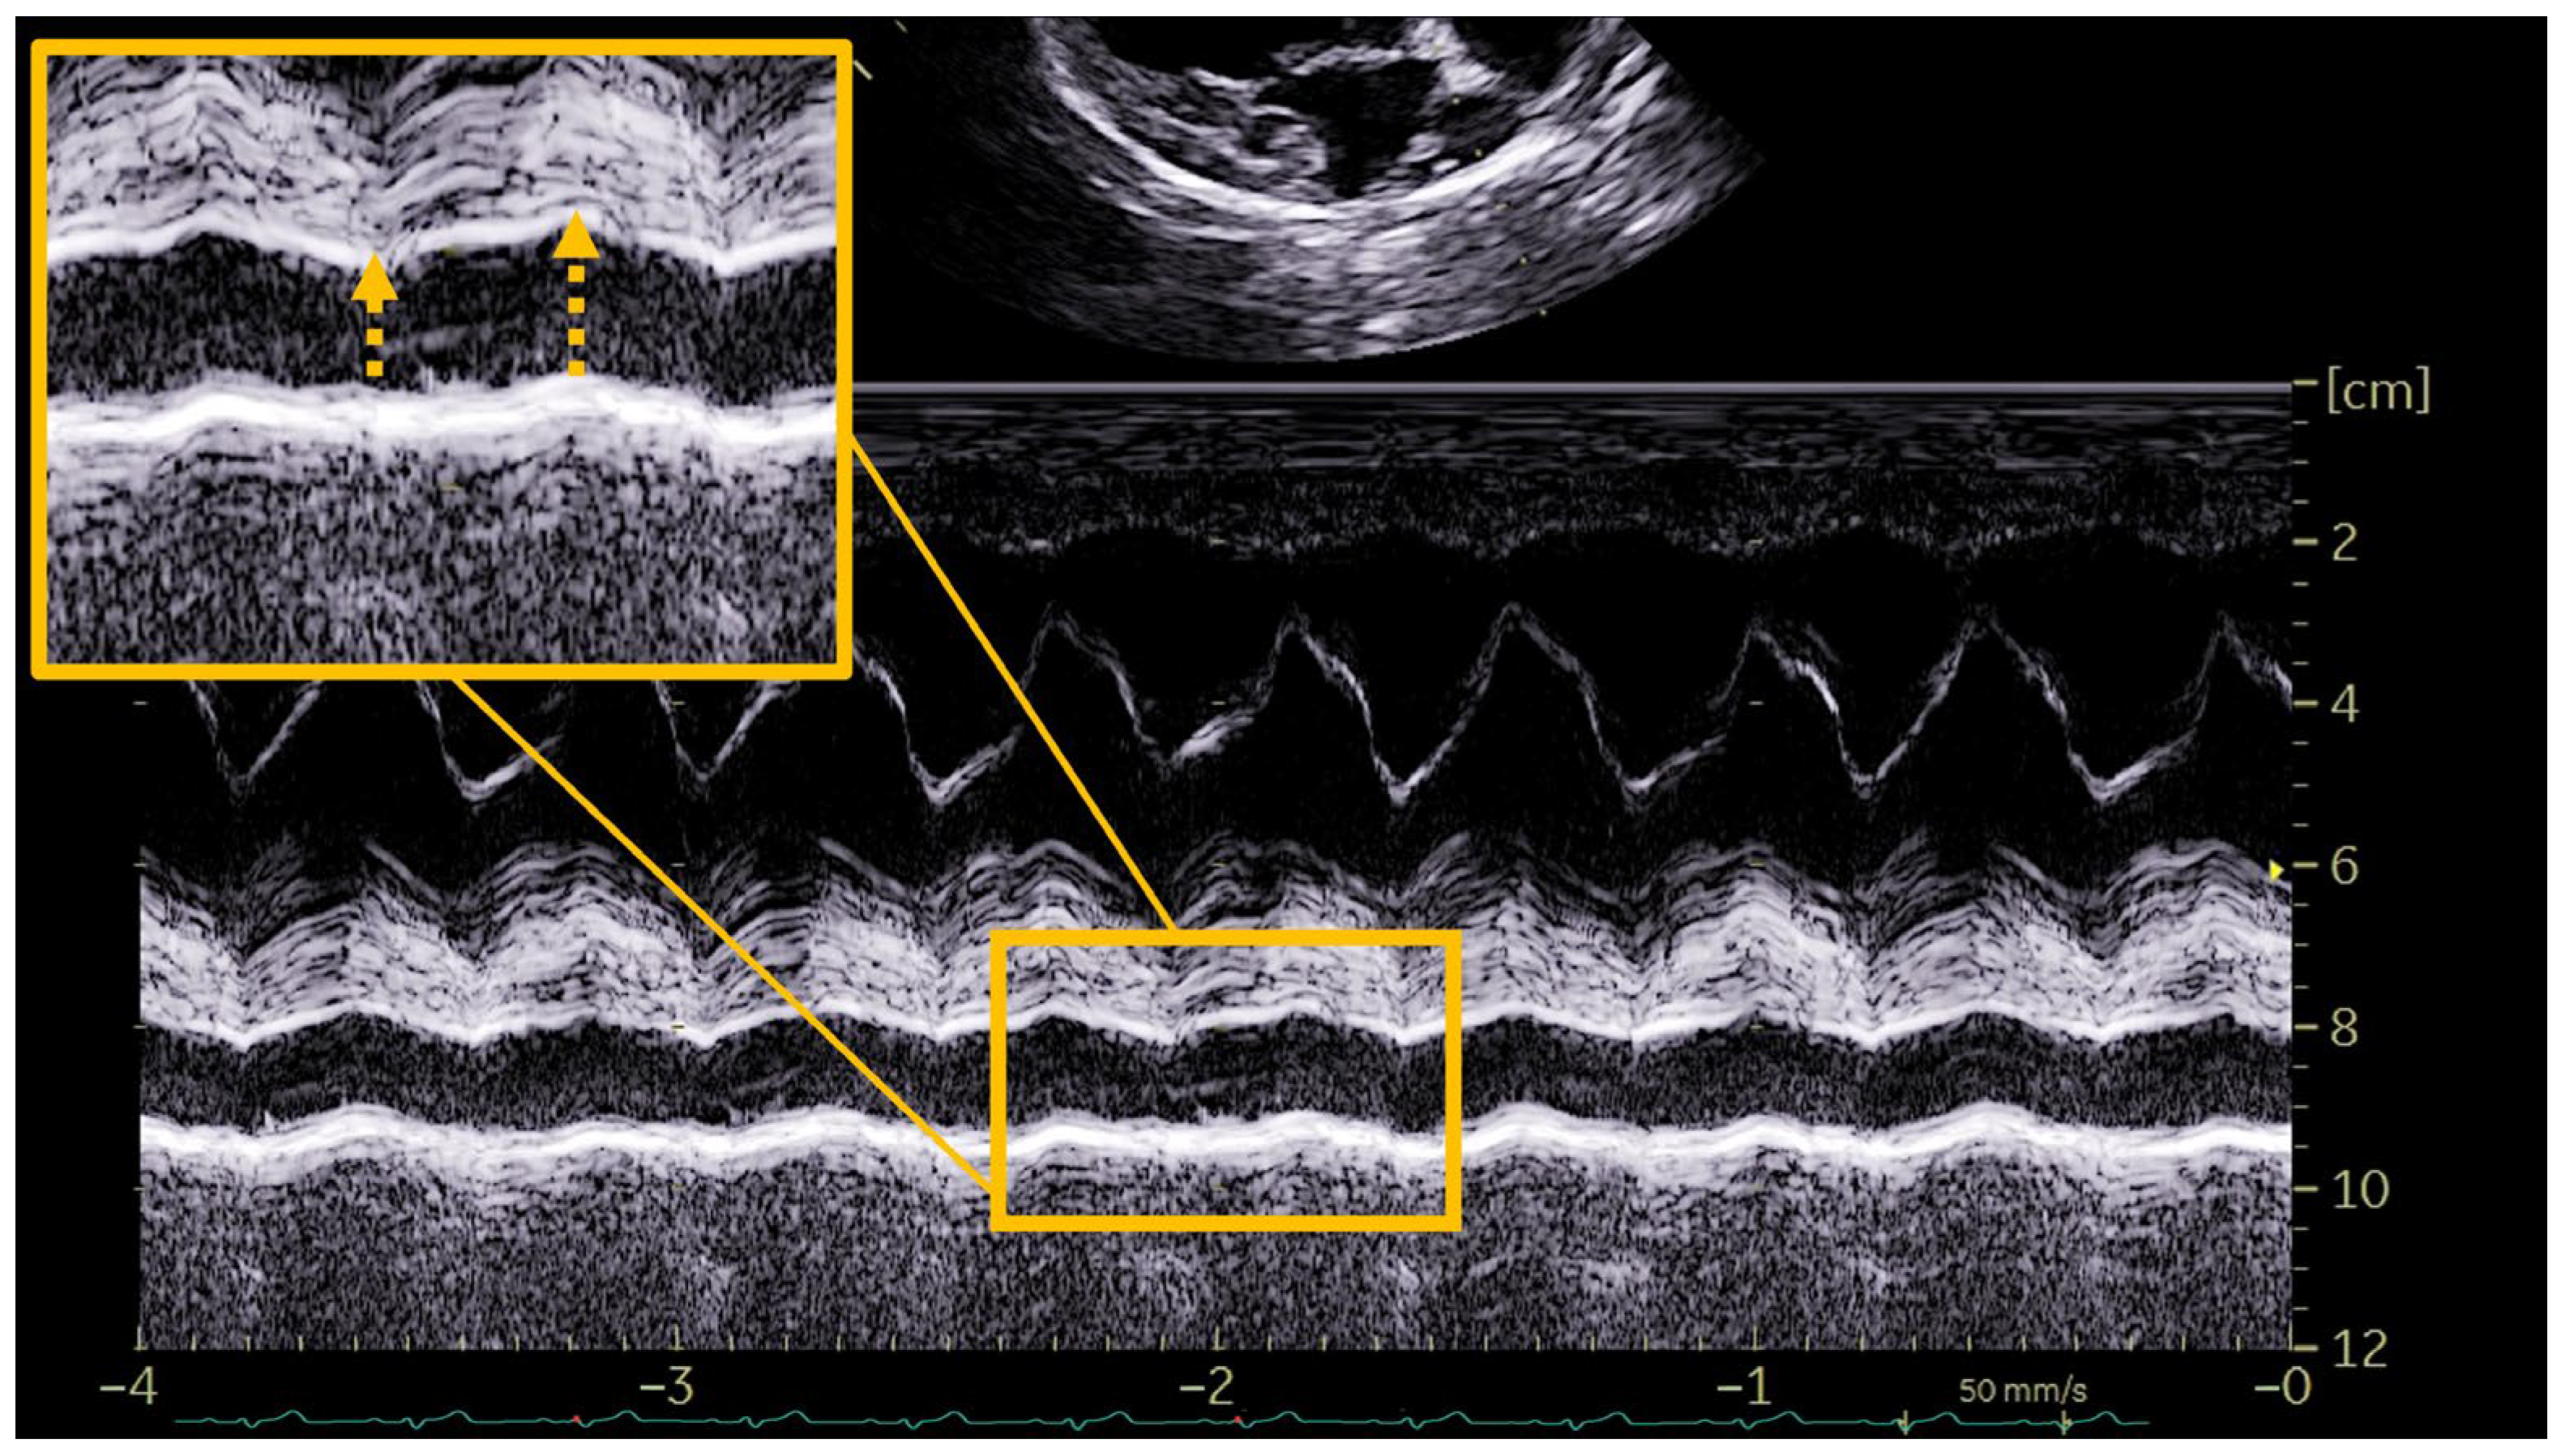

- Echocardiography